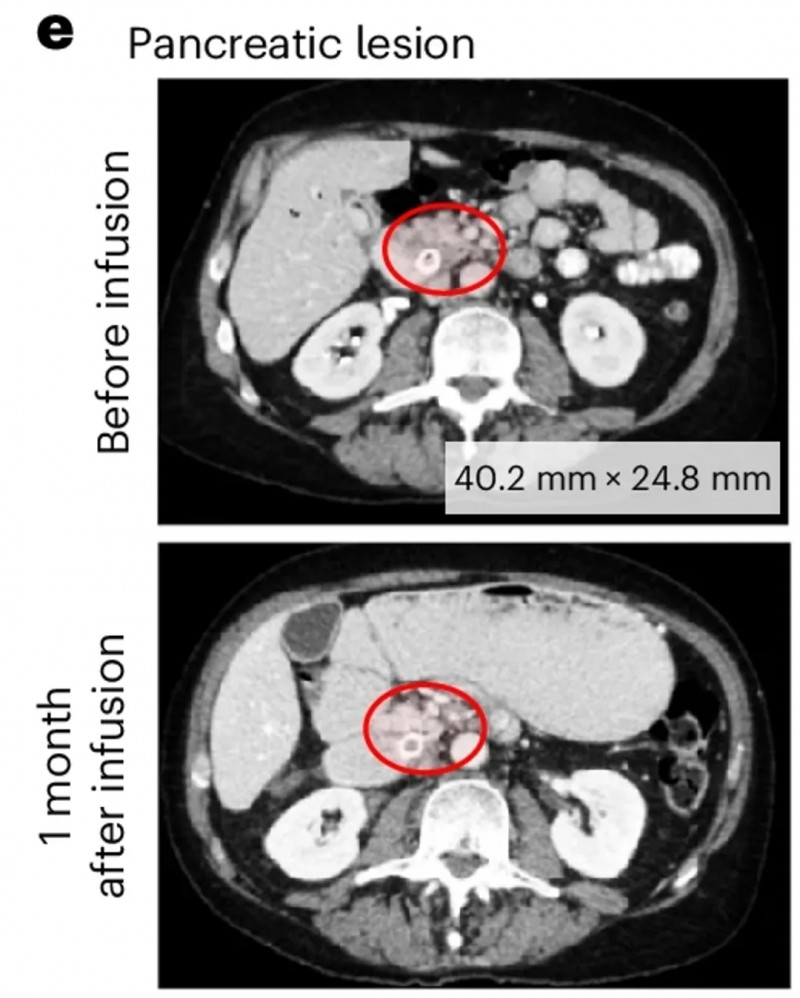

另一例为前列腺癌伴胰腺转移患者(UPN388):输注PSCA-CAR-T前后的CT复查显示,输注前病灶大小为40.2×24.8mm,输注后1个月病变完全消退、已无法测量(详见下图e);尽管因存在骨转移,RECIST评估结果为“病情稳定”,但患者软组织转移灶的放射学表现已有所改善(详见下图b)。

▲图源“Nature Medicine”,版权归原作者所有,如无意中侵犯了知识产权,请联系我们删除